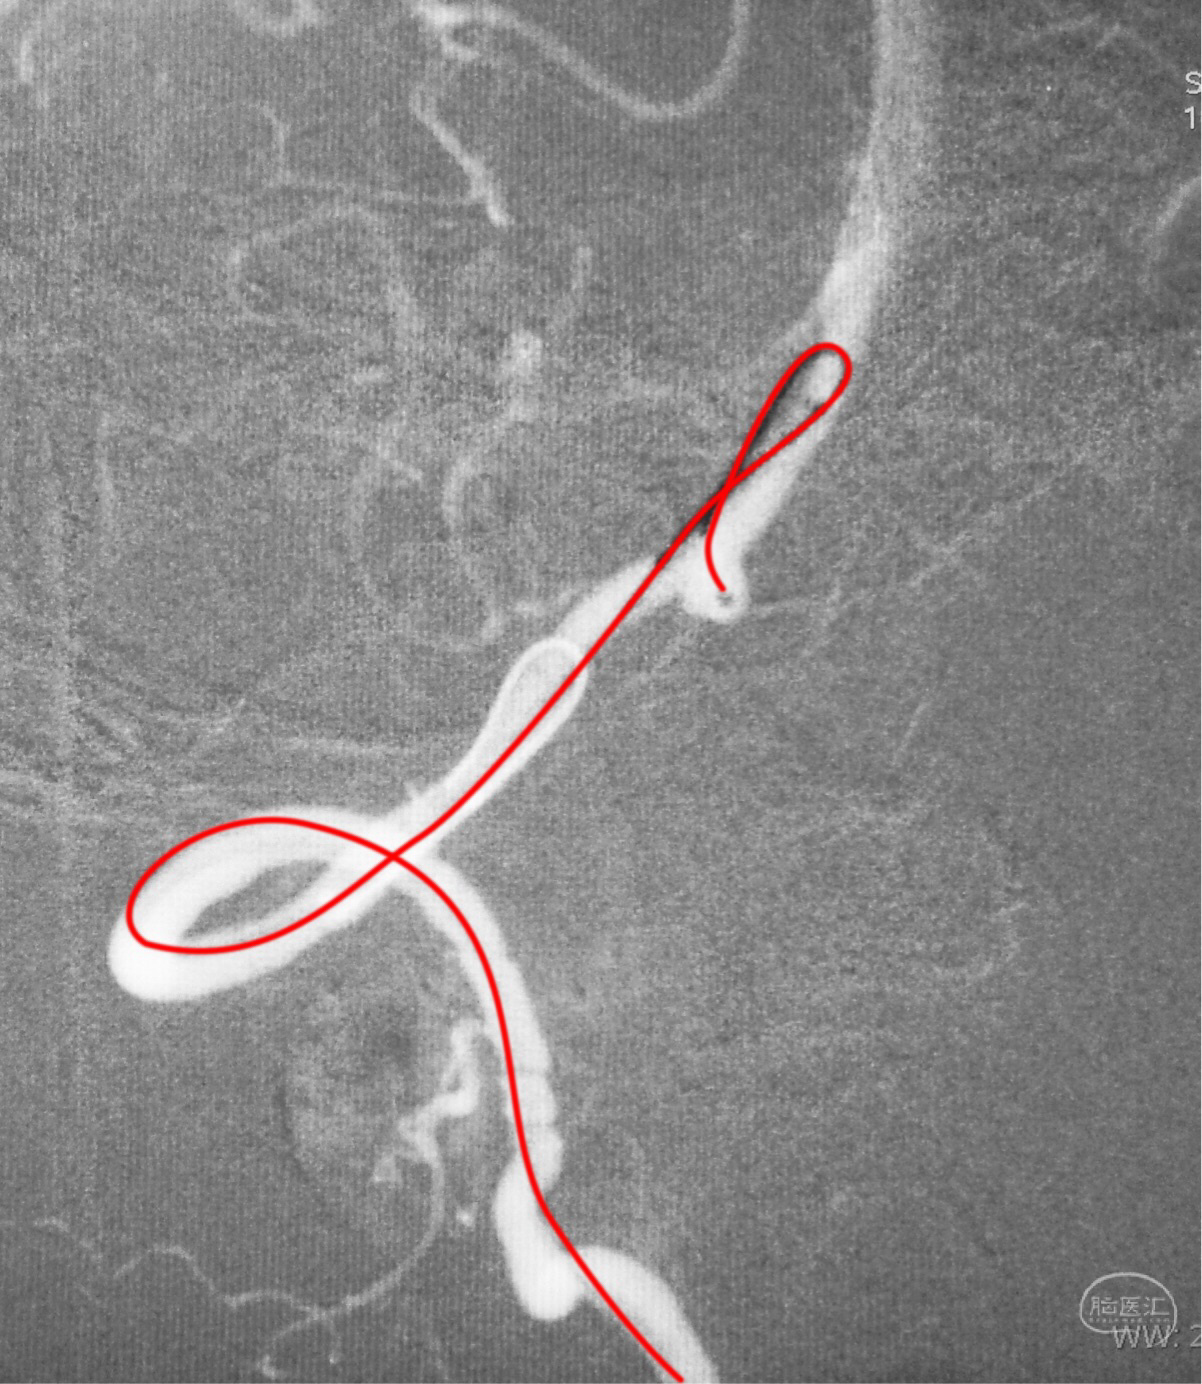

跨瘤颈释放Solitaire 4×20支架(蓝线),压住微导管(红线),在支架保护下经返折的微导管送入弹簧圈填塞瘤腔。

依次送入QC-2-4-3D,2-3-Helix,1.5-2-Helix,1.5-2-Helix四枚弹簧圈,最后一枚弹簧圈将管头(箭头)顶出瘤腔。

将Traxcess 14微导丝送入微导管,稍向远心端送微导管,使管头远离动脉瘤,再缓慢撤离。

解脱第一枚Solitaire 4×20支架后,套叠置入第二枚Solitaire 4×20支架,置入两枚支架的原因是考虑该瘤是夹层动脉瘤,多支架能够强化血流导向作用,有利于夹层愈合。